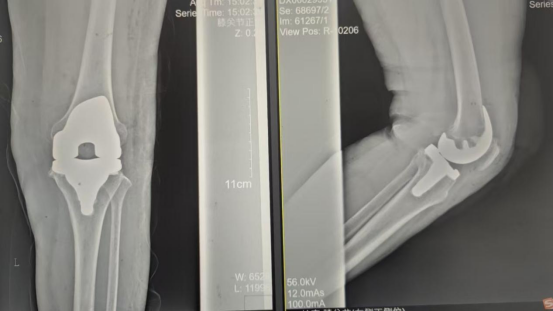

術(shù)后影像資料

因張女士患有高血壓病2級(jí)(高危)、心律失常(竇緩)且伴有肺部感染等并發(fā)癥。穆志亮主任和葉龍安主治醫(yī)師根據(jù)張女士的病情制定詳細(xì)手術(shù)方案,建議在全麻下行“左人工全膝關(guān)節(jié)置換術(shù)”。

手術(shù)當(dāng)天張女士懷著忐忑的心情進(jìn)入手術(shù)室,然而伴隨著麻醉醫(yī)師的和藹交談和手術(shù)護(hù)士的溫馨叮嚀,在不知不覺中慢慢睡著,手術(shù)非常順利。術(shù)后經(jīng)醫(yī)護(hù)人員的精心治療與護(hù)理,張女士康復(fù)出院,最終解決了10余年的病痛。